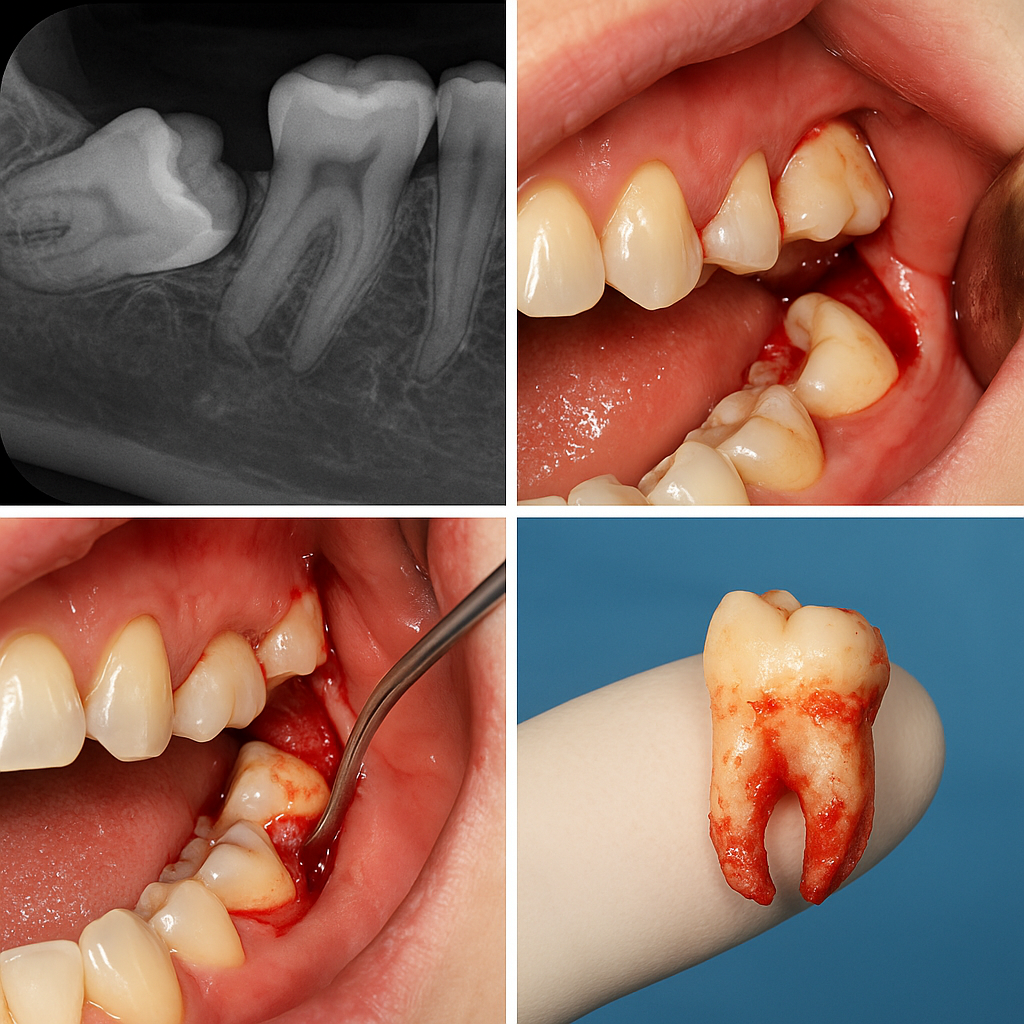

جراحی دندان نهفته چگونه انجام می‌شود؟

مراحل اصلی جراحی:

1. ارزیابی دقیق با CBCT یا رادیوگرافی پانورامیک

برای تعیین موقعیت دقیق دندان و نزدیکی آن به عصب یا سینوس

3. برش لثه و برداشت بافت استخوانی روی دندان

با استفاده از فرزهای جراحی و ابزار دقیق

4. خارج کردن دندان (گاهاً به‌صورت تکه‌تکه)

به‌ویژه در مواردی که دندان افقی یا خمیده است